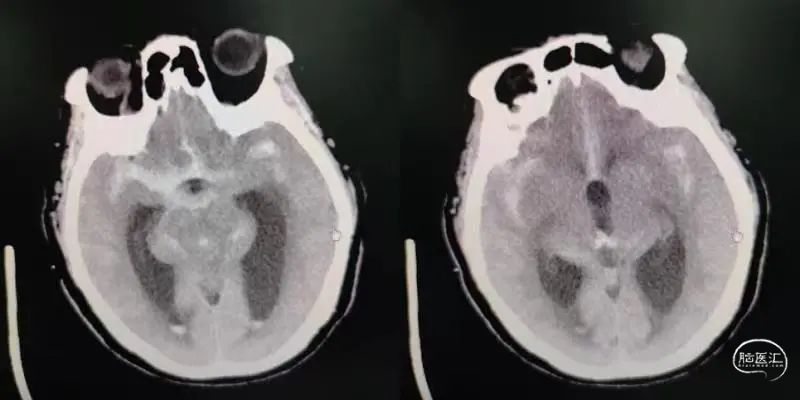

女性,81岁,SAH,HH分级2级,Fisher分级3级。

图1

术前DSA影像